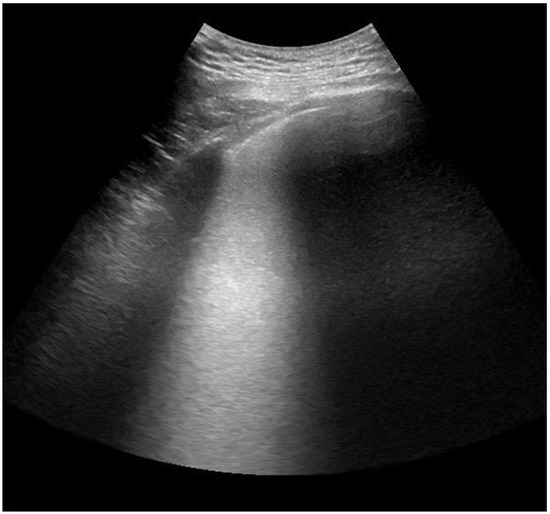

:1. Introduction

2.1. Study Design

2.4. Lung Ultrasonography and Score Assessment